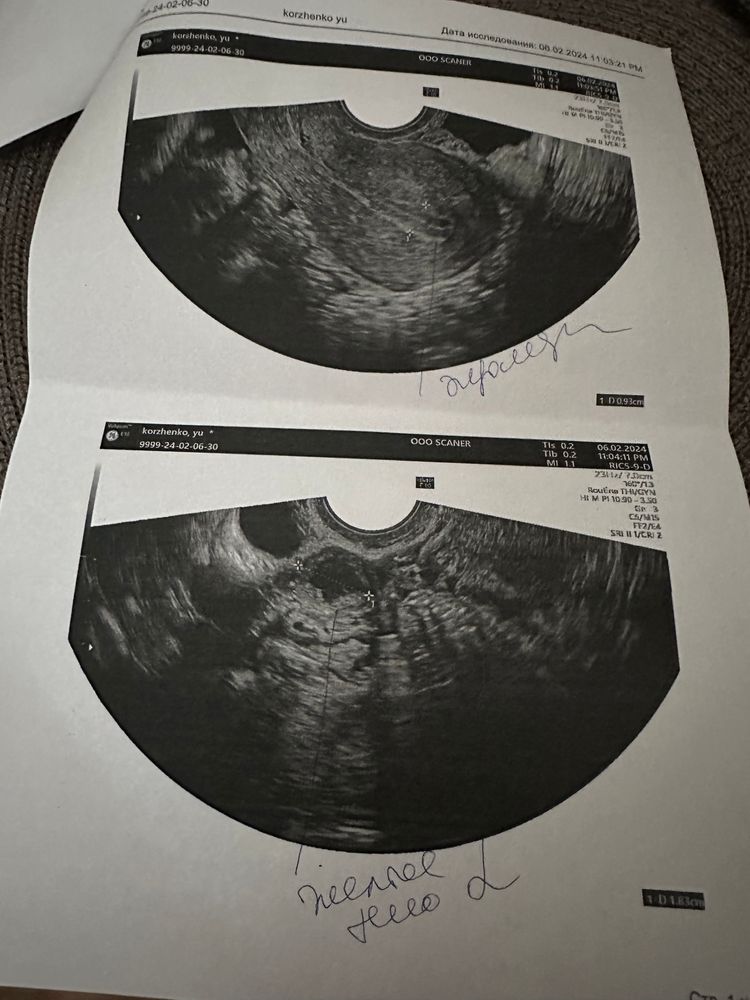

Девочки посмотрите сегодня была на фолликулометрии 12 день цикла,вроде как я поняла овуляция только случилась может ночью. Второй раз только на ней в жизни,если честно особо не понимаю.

Овуляция была)

Просто Катя, просто переживаю нормальный ли эндометрий,возможно ли зачатие? Очень хочется(

да, овуляция была и эндометрий нормальный) в моем случае были проблемы с овуляцией, и сначала я пила актиферт-гино, чтоб ее наладить. но тоже все получилось и как итог забеременела